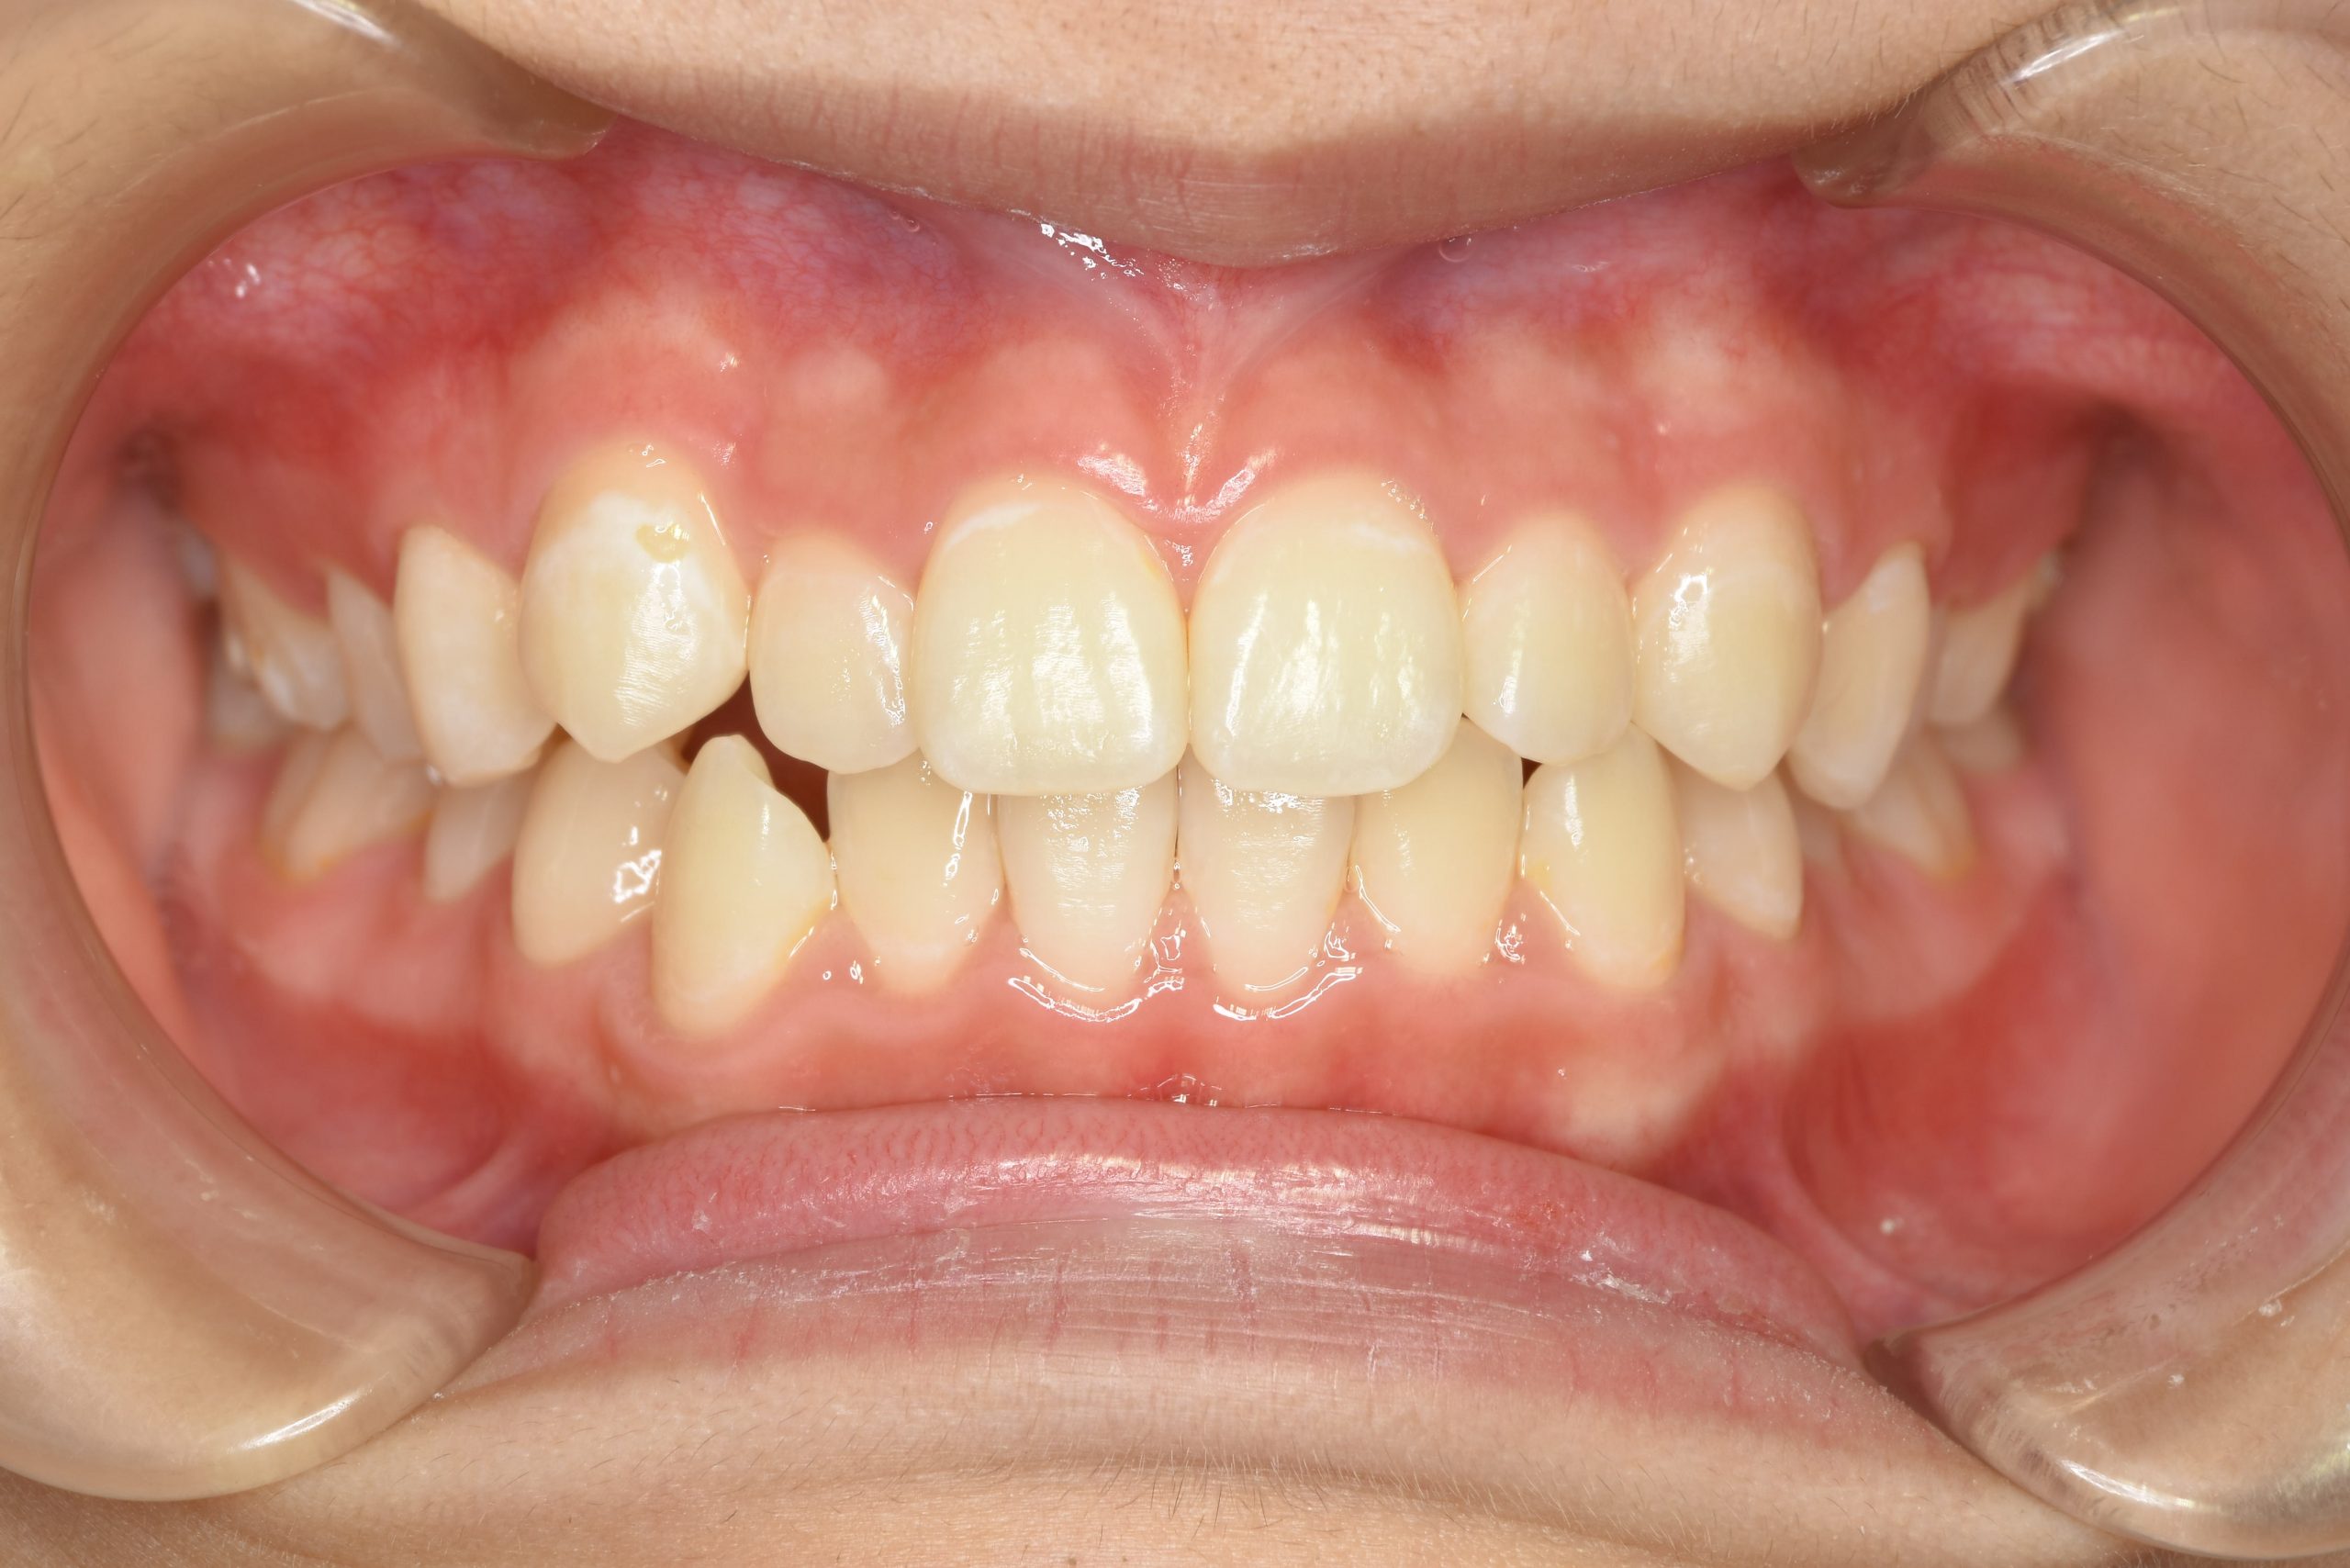

アフター

子どもの矯正治療|症例_169

施術内容 上顎急速拡大装置と下顎リンガルアーチを用いて上下顎骨を拡大した。

その後マウスピース型矯正装置で歯牙を配列し良好な咬合を獲得した。

治癒期間 3年5ヶ月間